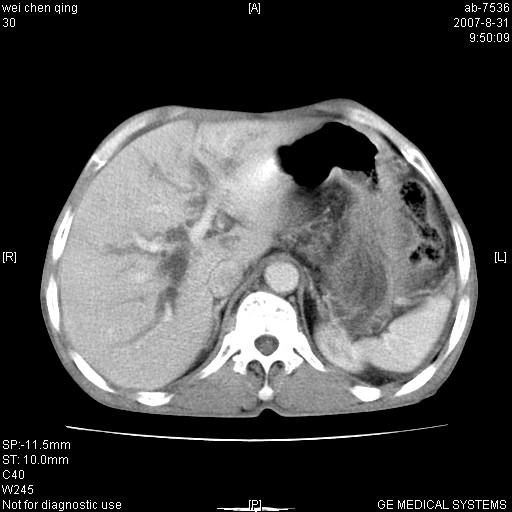

以下是引用zyyzzy在2007-8-31 14:34:00的发言:[br]该病人肝内胆管扩张,胆囊及胆总管未见明显扩张。在倒数第9层图像上可看到左右肝管结合部(肝总管)有软组织影,此处应薄层扫描。考虑肝总管占位(ca)、腹水。[br]